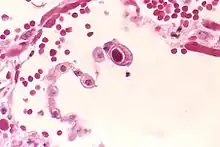

- Owl's eye appearance of inclusion bodies, which is highly specific for cytomegalovirus infection.[2]

The owl's eye appearance has a relationship with Reed–Sternberg cells in regards to cytomegalovirus infection.[4] Owl's eye appearance was used as an indication of the presence of the cytomegalovirus for the following case studies.

In 1982, a textbook wrote a chapter on cytomegalovirus and elaborated on its further relevance to owl's eye appearances.[5] It was stated that the owl's eye had a characteristic of a clear halo that extended towards the cell membrane's nucleus. The cellular structure was found to be relevant to pneumonia which was caused by cytomegalovirus.

In a 2000 case study, it was discovered that the owl's eye appearance as a cell body was key for the histopathological understanding of the cytomegalovirus.[2] The study found a strong relationship with a positive CMV PCR (p < 0.001).[2] The discovery led to a result that owl's eye appearances were a strong sign for finding cytomegalovirus inside organs.[2]

In 2012, a journal was written on patients with cytomegalovirus infection and was used in mapping out the owl's eye cells using their microscopic technology.[14] The patients were two elderly men at ages 75 and 77 years old. The image of the owl's eye appearance was created using the microscope via lasers, and two-dimensional images were created using computer software. The conclusion made by the journal was that the owl's eye had relevance to cytomegalovirus infection.